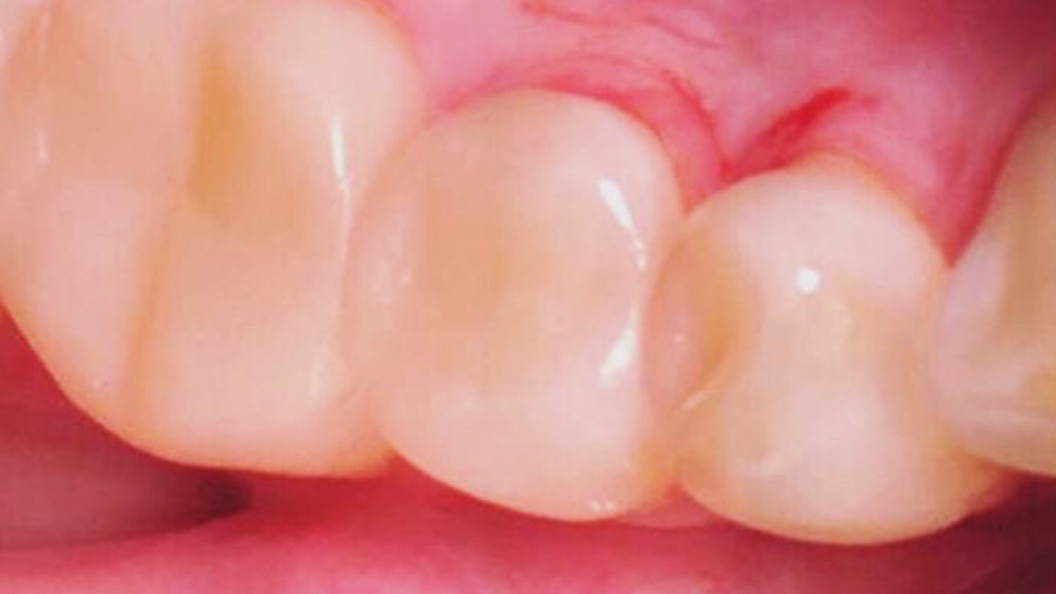

До и после лечения

Пациентка обратилась в «Стоматологию Комфорта» с жалобами на выпадение пломб зубов 44 и 45, болезненную реакцию на холодное и застревание пищи. В результате обследования врач Похилько Надежда Геннадьевна обнаружила глубокий кариес в районе зубов 44 и 45. Принято решение провести лечение с использованием композита светового отверждения Estelite.

- установка пломбы из композита светового отверждения Estelite.